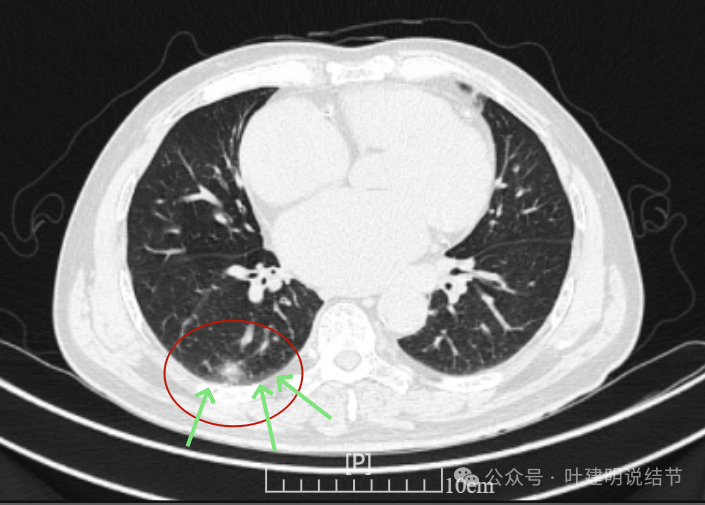

再看2024年6月时的影像:

右上没有明显变化,仍考虑良性可能性大。

左下也考虑良性,与2022年无明显变化。

右下新增病灶,混合密度,整体轮廓较清,瘤肺边界欠清。